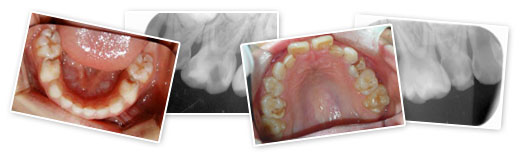

子供のお口は、歯が生えたり生え変わったりと環境には著しい変化があります。そして、その状況・環境によって虫歯のできやすい場所が異なってきます。

また、子供の歯は柔らかいので、大人に比べ虫歯の進行が早く、気がついたら大きな虫歯になっていたなどということもあります。

子供たちのお口の環境は成長するにつれ、「歯の生え変わり」「顎の成長」など著しい変化がありますから、虫歯の予防はもちろん、歯並びや噛み合わせなどの診査も必要になってきます。